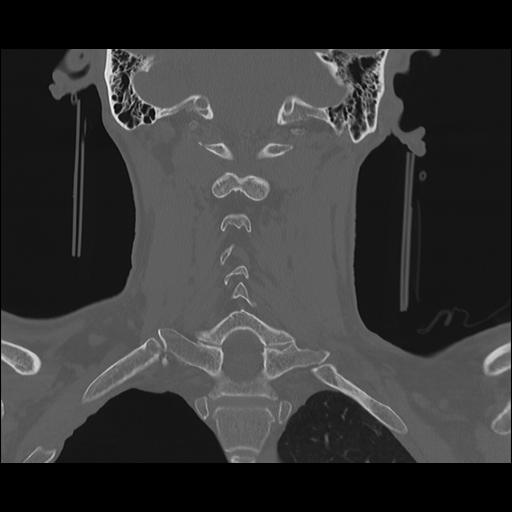

16 HUESO,,Coronal,2.000,HUESO,Coronal,